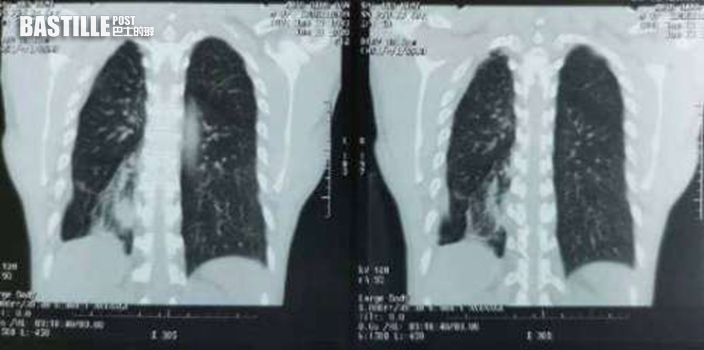

據內地傳媒報道,西安一名40歲男子過去10多年來飽受咳嗽、咳痰問題困擾,近一年惡化成痰中帶血,就連血量也逐漸增加、呈現鮮紅色,於是到西安市中心醫院呼吸與危重症醫學科求診,經胸部X光檢查後發現氣管裡藏有異物。